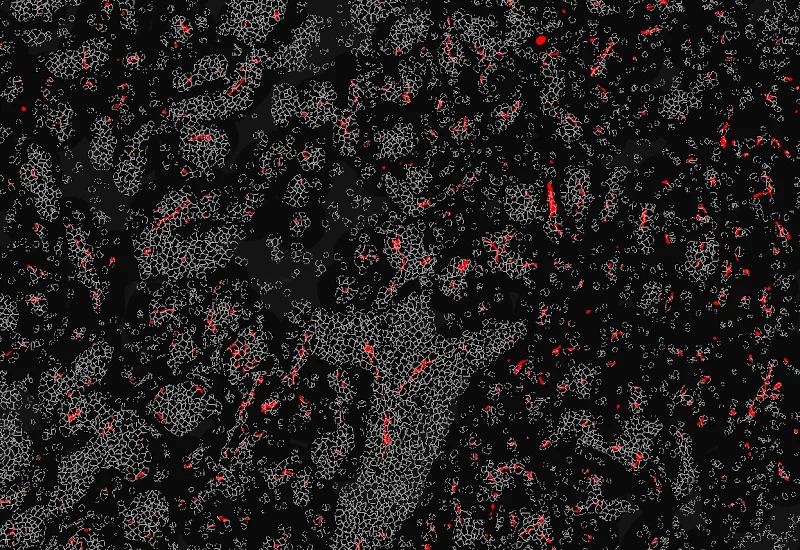

Nuclei detection

Tumor foci detection

Vessel detection

Blood vessels distance

Vessel proximities

The IF Tumor Foci Angio App is able to identify single cells as well as to segment tissues into tumor foci and blood vessels based on appropriate markers. It applies proximity maps to identify nuclei close to blood vessels. It measures the number of nuclei that are at a certain distance relative to blood vessels, the number of nuclei in the different morphological entities and the area of the morphological entities.

Detect single nuclei and segment tissue into tumor foci and blood vessels, apply proximity mapping to quantify nuclei distances to vessels, and measure compartment areas and nuclei distribution.